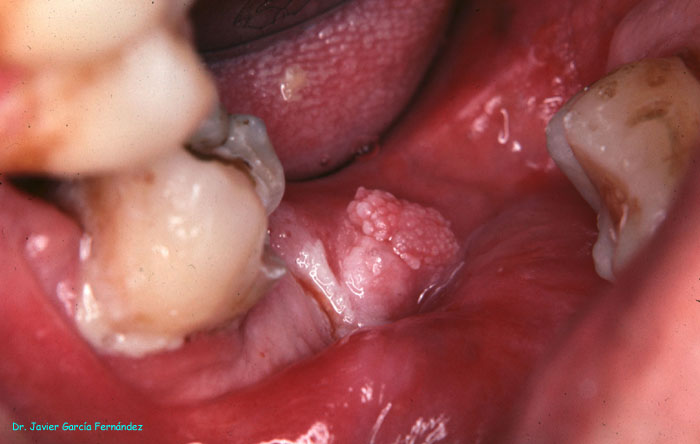

Atlas of Surgical Techniques in Periodontics. Chapter I. Diagnostic of Peridontal Diseases. Classification. Atlas de Técnicas Quirúrgicas en Periodoncia. Cap. I. Classification. Atlas de Técnicas Quirúrgicas en Periodoncia